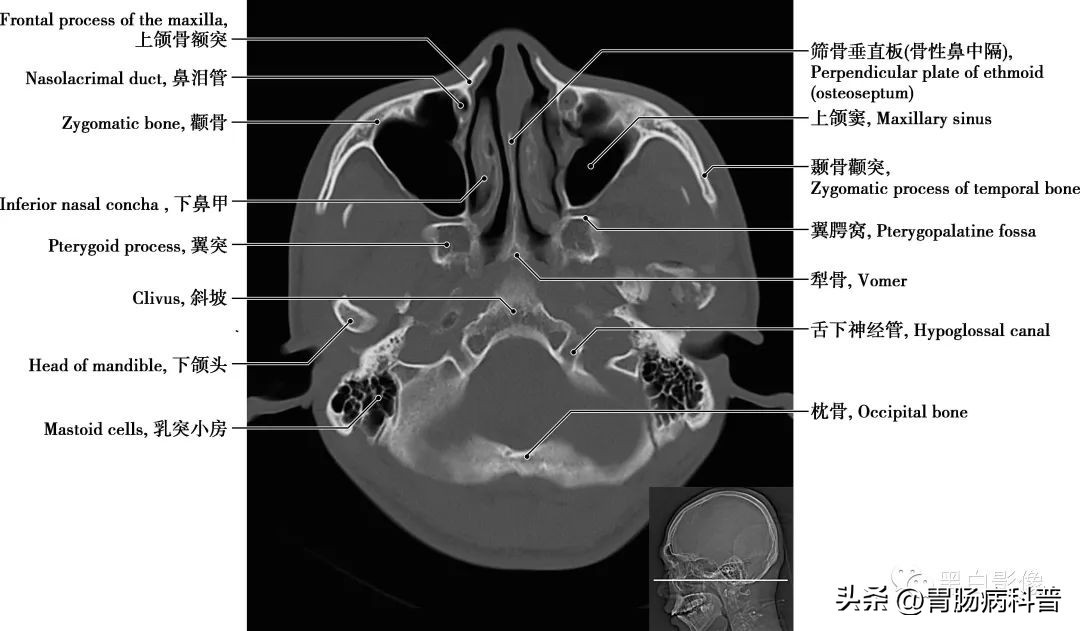

图1-1-18 经下颌头轴位切面

枕大池 又称小脑延髓池,位于颅后窝的后下部,小脑下面、延髓背侧面与枕鳞下部三者之间。向前经小脑溪通第四脑室;向前外经延髓侧面通延髓池。咽鼓管 咽鼓管从鼓室口向内、向前、向下直到咽口,是沟通鼓室与鼻咽部的通道,软骨部平时闭合,仅在吞咽或呵欠时开放,以平衡中耳和外耳的气压,有利于鼓膜的正常振动

图1-1-19 经小脑扁桃体轴位切面

上颌窦 为上颌骨体内的锥形空腔,位于上颌骨体内,窦壁为骨质,覆黏膜,向内侧开口于中鼻道,分为一底、一尖及前、后、上、下四个壁。由于窦口高于窦底部,故在直立位时若有炎性物不易自然流出。外耳道 为外耳门至鼓膜的管道,呈弯曲状,由外向内,先向前上,继而稍向后,弯向前下